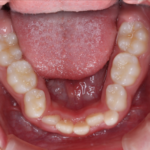

反対咬合(受け口)の症例

Before After 治療途中の小児矯正の症例です。 成長期に上顎の幅を広げ ...